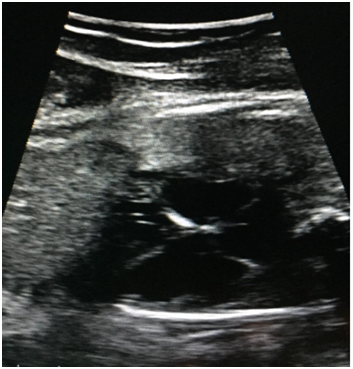

On admission to HUCSR fetal well tests which are performed are normal, then ultrasound detail in which no signs of fetal hydrops or other anatomical abnormalities observed is performed. Finally fetal echocardiogram where situs solitus, normal vascular situs, cardiac shaft 45, cardiothoracic ratio 0.55, cut normal four chambers, atrioventricular and ventriculoarterial accordance normal valve insertion, patent foramen ovale, flow to the left atrium, movements walls is performed free ventricles of normal amplitude, hyperechoic observed level suggestive sinoatrial node endocardial fibroelastosis (Figure 1). No evidence sinus rhythm, atrioventricular dissociation documented in M ​​(Figure 2) Mode, with ventricular heart rate 50bpm and 135bpm atrial rate, PR segments variables, aortic isthmus with antegrade flow. There is no evidence of diastolic dysfunction given normal venous ductus.

Figure 1 Photograph of four-chamber where hyperechogenicity evidenced sinoatrial level and tricuspid calcification secondary to the healing process, indicating endocardial fibroelastosis valve.